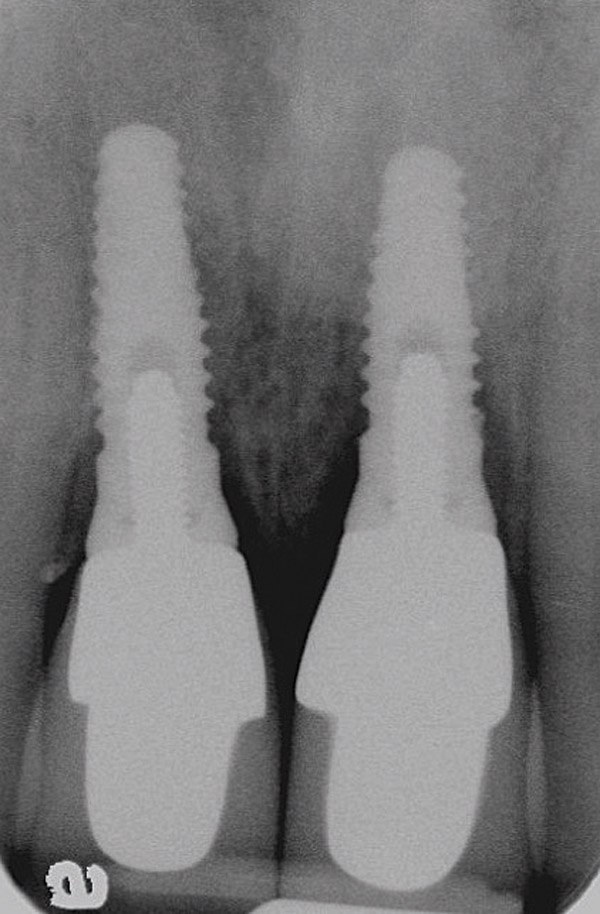

Figure 3  Periapical radiograph of implants in the Nos. 8 and 9 sites 3 years after placement. A bony peak was still present between the implants due to successful guided bone regeneration and favorable fixture spacing.

Figure 3

Figure 4  Final restoration of implants in the Nos. 8 and 9 sites 3 years after placement. Note the short central papilla regardless of the presence of bone. Restoration courtesy of Dr. Alan Goldberg.

Figure 4